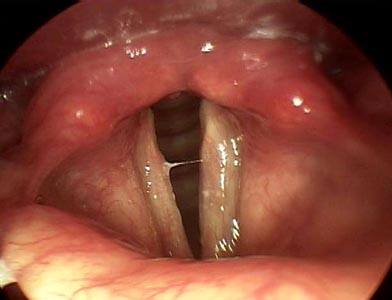

Воспаление гортани при ларингите

Под ларингитом подразумевают воспалительный процесс, локализованный в слизистой оболочке гортани. По форме различают острый и хронический ларингит. О хроническом ларингите говорят при длительности воспалительного процесса более 2 недель.

Острый ларингит сопровождается сухостью и першением в гортани, ощущением царапания, а иногда и болезненностью глотания. Для острого процесса характерен надсадный сухой кашель. Наблюдается осиплость голоса, вплоть до его пропадания, что происходит из-за потери способности голосовых связок к вибрации. Явления интоксикации при остром ларингите, включающие в первую очередь головную боль и повышение температуры, длятся до 10-14 дней. Разновидностью острого ларингита является подскладочный (подсвязочный) ларингит, представляющий собой опасность вследствие возможного развития стеноза гортани, что называется ложным крупом. Для хронического ларингита характерны те же признаки, сохраняющиеся в течение более 2-х недель. Развивается диффузное воспаление, а в результате отека и гиперемии слизистой оболочки гортани происходит неполное закрытие голосовой щели. При обнаружении мелкоточечных кровоизлияний на слизистой гортани диагностируют геморрагический ларингит.